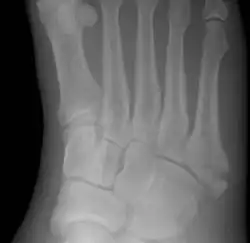

Jones fracture

| Jones fracture as seen on Xray | |

A Jones fracture is a broken bone in a specific part of the fifth metatarsal of the foot between the base and middle part .[8] In general, fifth metatarsal fractures heal readily, but a Jones fracture must be recognized and accurately diagnosed because of its higher rate of delayed healing or nonunion.[4] It results in pain near the midportion of the foot on the outside.[2] There may also be bruising and difficulty walking.[3] Onset is generally sudden.[4]

The fracture typically occurs when the toes are pointed and the foot bends inwards.[6][2] This movement may occur when changing direction while the heel is off the ground such in dancing, tennis, or basketball.[9][10] Diagnosis is generally suspected based on symptoms and confirmed with X-rays.[3]

A person with a Jones fracture may not realize that a fracture has occurred. Diagnosis includes the palpation of an intact fibularis brevis tendon, and demonstration of local tenderness distal to the tuberosity of the fifth metatarsal, and localized over the shaft of the proximal metatarsal.

Diagnostic X-rays include anteroposterior, oblique, and lateral views and should be made with the foot in full flexion.